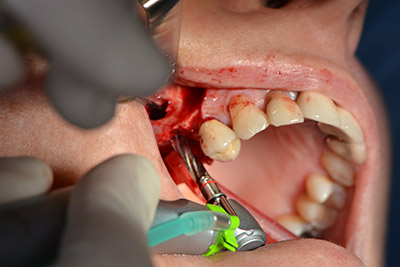

Хирургична процедура за имплантиране

Класическият разрез (крестално, букално освобождаване) и подготовката на мукопериостално ламбо осигуряват добра видимост.

Импланти Sky (Bredent) са използвани в този случай. Хирургичният протокол за тях изисква пилотно пробиване с дрил при 1200 rpm (Фиг. 9).